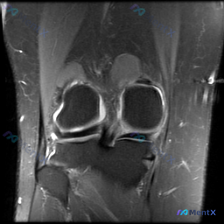

这是一份膝关节MRI的冠状位T2加权序列影像,初始问题是观察是否存在软骨异常,我们基于现有影像信息做完整分析。

- 内侧间室:内侧半月板体内可见明显高信号,且高信号穿透了半月板关节面(体部区域),这是半月板撕裂的典型影像学表现;内侧关节间隙周围可见局部高信号,提示周围软组织水肿或韧带损伤。

- 外侧间室:形态相对完整,未见明显异常信号。

- 其他结构:关节腔未见明显过量积液,股骨髁和胫骨平台骨皮质连续性好,无明显骨折线或大面积骨髓水肿;前后交叉韧带走行区域可见,本切面未见明显韧带中断信号。

初始问题指向「软骨异常」,但我们读片后发现,影像上最突出、证据最充分的病变并不是软骨,而是内侧半月板的结构异常,因此我们需要把分析焦点修正为「膝关节内侧症状相关的结构性损伤」。

结合影像信息,我们可以得到初步结论:本影像最主要的病变是内侧半月板撕裂,同时不能排除合并内侧副韧带损伤;初始提到的软骨异常更可能是继发改变或伴随退变,不是本影像的核心病变。